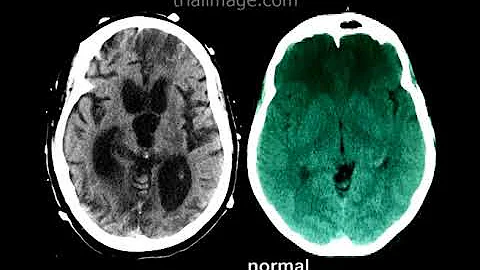

Treatment of Hydrocephalus by placement of a shunt into the ventricles of the brain (ventricular peritoneal shunt). Possible ...